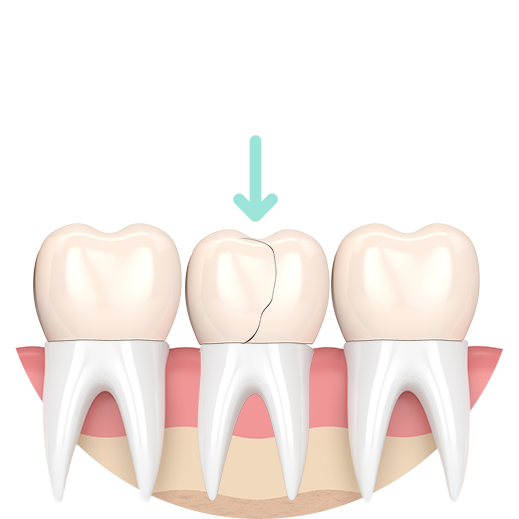

Preparation for a Crown

Damaged natural crown

Reshaped tooth

Porcelain crown